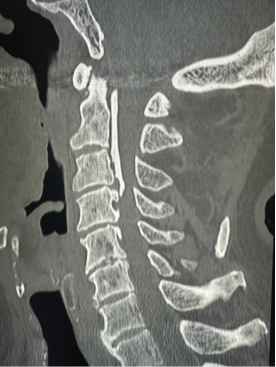

Common diagnostic tests include:

- X-rays (to assess spinal alignment and bending points)

- CT scans (for bony structures and abnormalities)

- MRI scans (to examine nerve and soft tissue damage)

- Blood tests (to check for neurological or autoimmune disorders such as Parkinson's disease)

Because DHS can mimic other diseases, an experienced specialist is necessary for an accurate diagnosis.